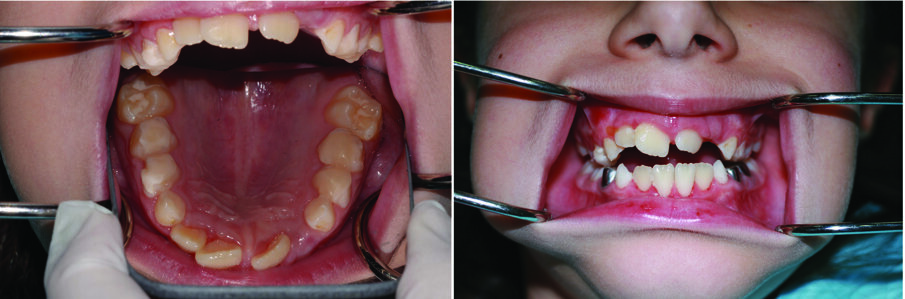

A Case Report

An eight and half year-old girl (LT) attended the paediatric dentistry department of Hamdan Bin Mohammed College of Dental Medicine (HBMCDM) in Dubai Healthcare City for an opinion. The patient’s mother was concerned about the delayed eruption of an upper front tooth (21) that was affecting her child’s appearance (Figs. 1 a, b & c). LT was medically fit and healthy with no history of previous dental trauma. She was in the mixed dentition stage. Tooth 11 had erupted 4 months ago in cross bite but 21 had not erupted yet. Its eruption was much delayed (usually erupts at 7 ½ years of age). Looking back at previous x-rays, a DPT was taken a year ago and it was noticed that an important feature was missed. Retrospectively, the presence of a supernumerary tooth ($) in the area of 21 and congenital missing 47 was confirmed (Fig. 2). Two new x-rays, namely upper intra oral periapicals and the parallax technique (distal shift) showed a supernumerary tooth (conical and inverted) in a palatal position (Figs. 3 a & b). LT also had dental caries of her primary teeth (Figs. 4 a & b), had a pronounced gag reflex and was dentally anxious.

The patient had a Class I skeletal and molar relationship, with a slight rotation and anterior crossbite of 11. Due to the complex nature of this case, requiring a multidisciplinary approach, a joint orthodontic-paediatric dentistry case conference was arranged, and a diagnostic list and treatment plan was formulated.

Figs. 1 (a, b & c). An 8 ½ year old girl presented with delayed eruption of 21 and a palpable palatal swelling. Lower teeth were carious; see bitewings in Figure 4

At one-week follow up, the patient was reviewed. She had no complaints. Tooth 21 had begun to erupt (Fig. 12). At one month’s follow up, tooth 21 had erupted in cross bite. Tooth 11 was already in cross bite.

This would allow for spontaneous correction of the anterior cross bite of 21 due to the positive pressure of the patient’s tongue. At two-month follow up, tooth 21 had moved but was still in cross bite. We placed a composite ramp/restoration on 31 incisally, to finalise the correction of the cross bite. One month later, tooth 21 was over the bite and in the correct anterior-posterior position (Fig. 16 a & b).